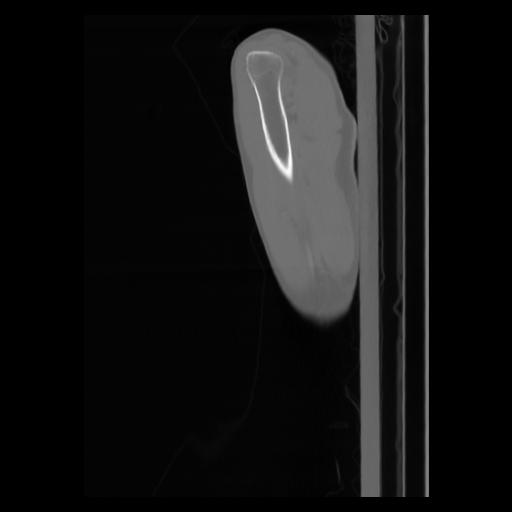

30 CUERPO,CE,Sagittal,3.000,CUERPO,Sagittal,